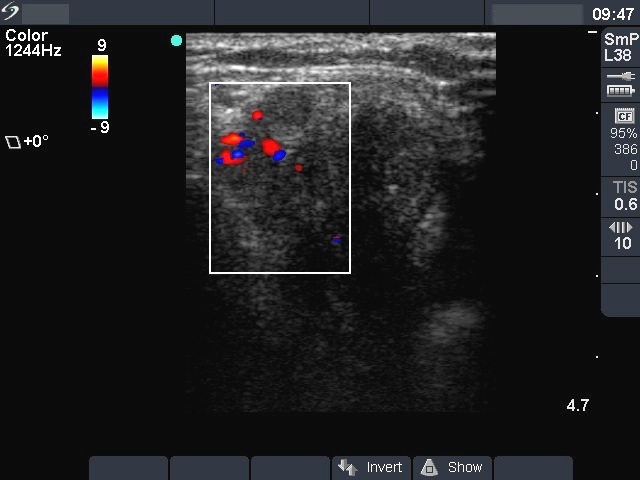

Ultrasonography. The entire left lobe was composed of multiple hypoechogenic nodules with irregular borders. They contained coarse and microcalcifications, too. A similar lesion was in the jugular area. Multiple metastatic lymph nodes were present in the left side of the neck.